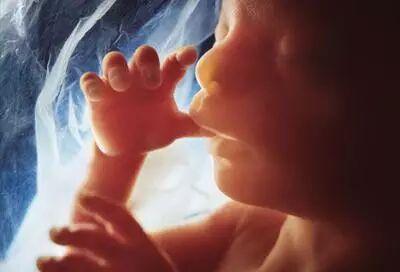

五个月:

艰辛而幸福的孕育历程已经走过一半了。这时有一种油腻的白色物质覆盖着胎儿的全身,这种物质叫做胎儿皮脂,它能够保护胎儿长期浸没在羊水中的皮肤,还可以在生产时减少宝宝经过产道的阻力。